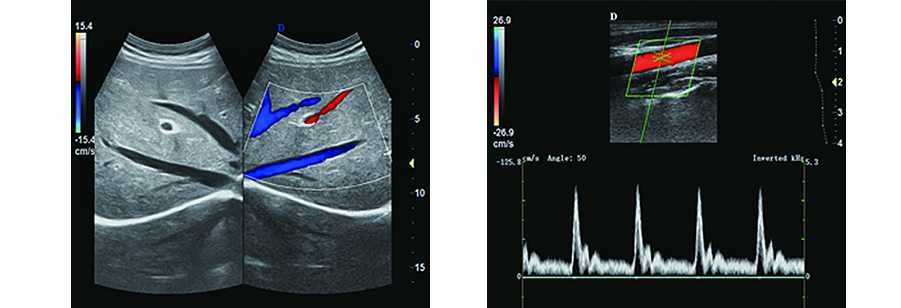

2.血管應用:多種高頻探頭可用于血管檢查,支持彩色和PW、三同步、聲束偏轉、角度校正、2D/彩色同步顯示以及方便快捷的測量和報告